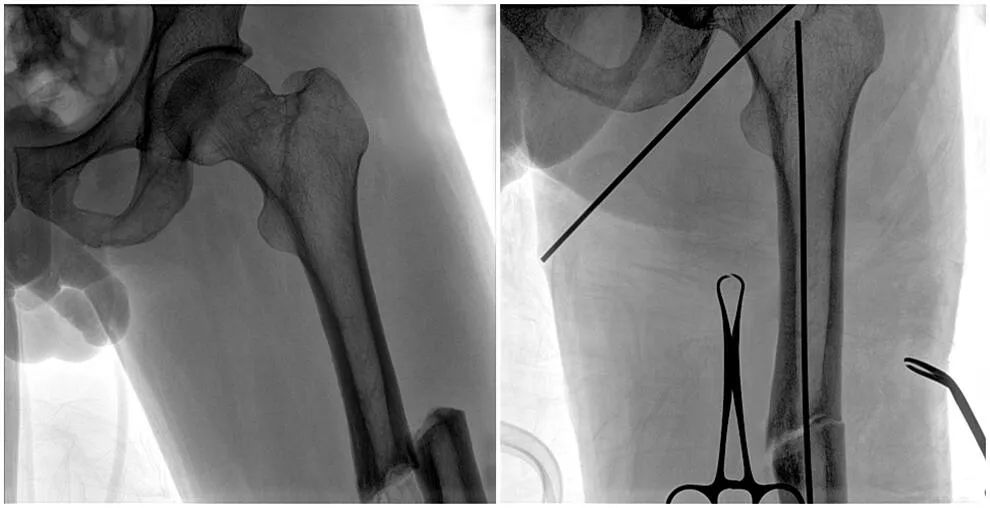

C形臂辅助手术过程

术中使用普爱医疗大平板一体式C形臂进行透视,判断骨折情况及克氏针、髓内钉等金属植入物的位置,进行调整。C形臂准确的术中定位,大大缩短了手术的时间,减轻了患者的痛苦,辅助手术顺利完成。

在进行髓内钉内固定术时,医生需要同时观察到入钉点和骨折部位的情况,普爱医疗大平板一体式C形臂采用30CM×30CM的平板探测器,能够呈现更广阔的成像面积,满足大部分长骨髓内钉内固定术的摄片需求。